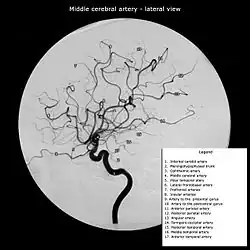

The leptomeningeal collateral circulation (also known as leptomeningeal anastomoses or pial collaterals) is a network of small blood vessels in the brain that connects branches of the middle, anterior and posterior cerebral arteries (MCA, ACA, and PCA),[1] with variation in its precise anatomy between individuals.[2] During a stroke, leptomeningeal collateral vessels allow limited blood flow when other, larger blood vessels provide inadequate blood supply to a part of the brain.[3]

Inter-territorial end to end anastomoses exist between branches of the anterior cerebral artery and middle cerebral artery, the posterior cerebral artery and middle cerebral artery, the anterior cerebral artery and posterior cerebral artery, and the right and left anterior cerebral arteries.[7][8][9][10] Intra-territorial anastamoses connect adjacent arterial branches within the same arterial territory (between two branches of the same middle cerebral artery, for example).[5]

During an ischaemic stroke, blood flow through a cerebral artery is compromised. This frequently causes substantial injury to the area of the brain supplied by the artery, but not all of this territory is necessarily affected. A post mortem study of middle cerebral artery strokes demonstrated that the area of brain injury was often smaller than the total area supplied by the middle cerebral artery. Leptomeningeal collateral vessels from the anterior cerebral artery and posterior cerebral artery appeared to allow for perfusion of some brain tissue to persist, partially compensating for the loss of the major vessel.[6] This compensatory effect is however usually inadequate to maintain a normal blood supply.[11]

A 2016 study compared patients awaiting carotid artery stenting for unilateral atherosclerotic plaques. Those with leptomeningeal collaterals evident on cranial angiography had a higher incidence of intracranial haemorrhage (ICH) after stenting. The authors argued that the presence of such collaterals on imaging should be considered a risk factor for ICH in patients where carotid stenting is otherwise indicated.[14]

Descriptions of leptomeningeal collateral vessels are found in Thomas Willis’ Cerebri Anatome (1664).[15][16] German physician Otto Heubner first demonstrated their presence in his 1874 work Die luetische Erkrankung Der Hirnaterien.[17] He injected the middle cerebral artery, anterior cerebral artery and posterior cerebral artery in turn, in an attempt to establish the territories these arteries supply. Even when other anastomoses from the circle of Willis were blocked off, the whole cerebral arterial tree could be filled.[1] Later study in the 1950s and 60s by H.M. Vander Eecken and R.D. Adams provided a comprehensive review of the anatomy of the leptomeningeal collateral circulation.[6]